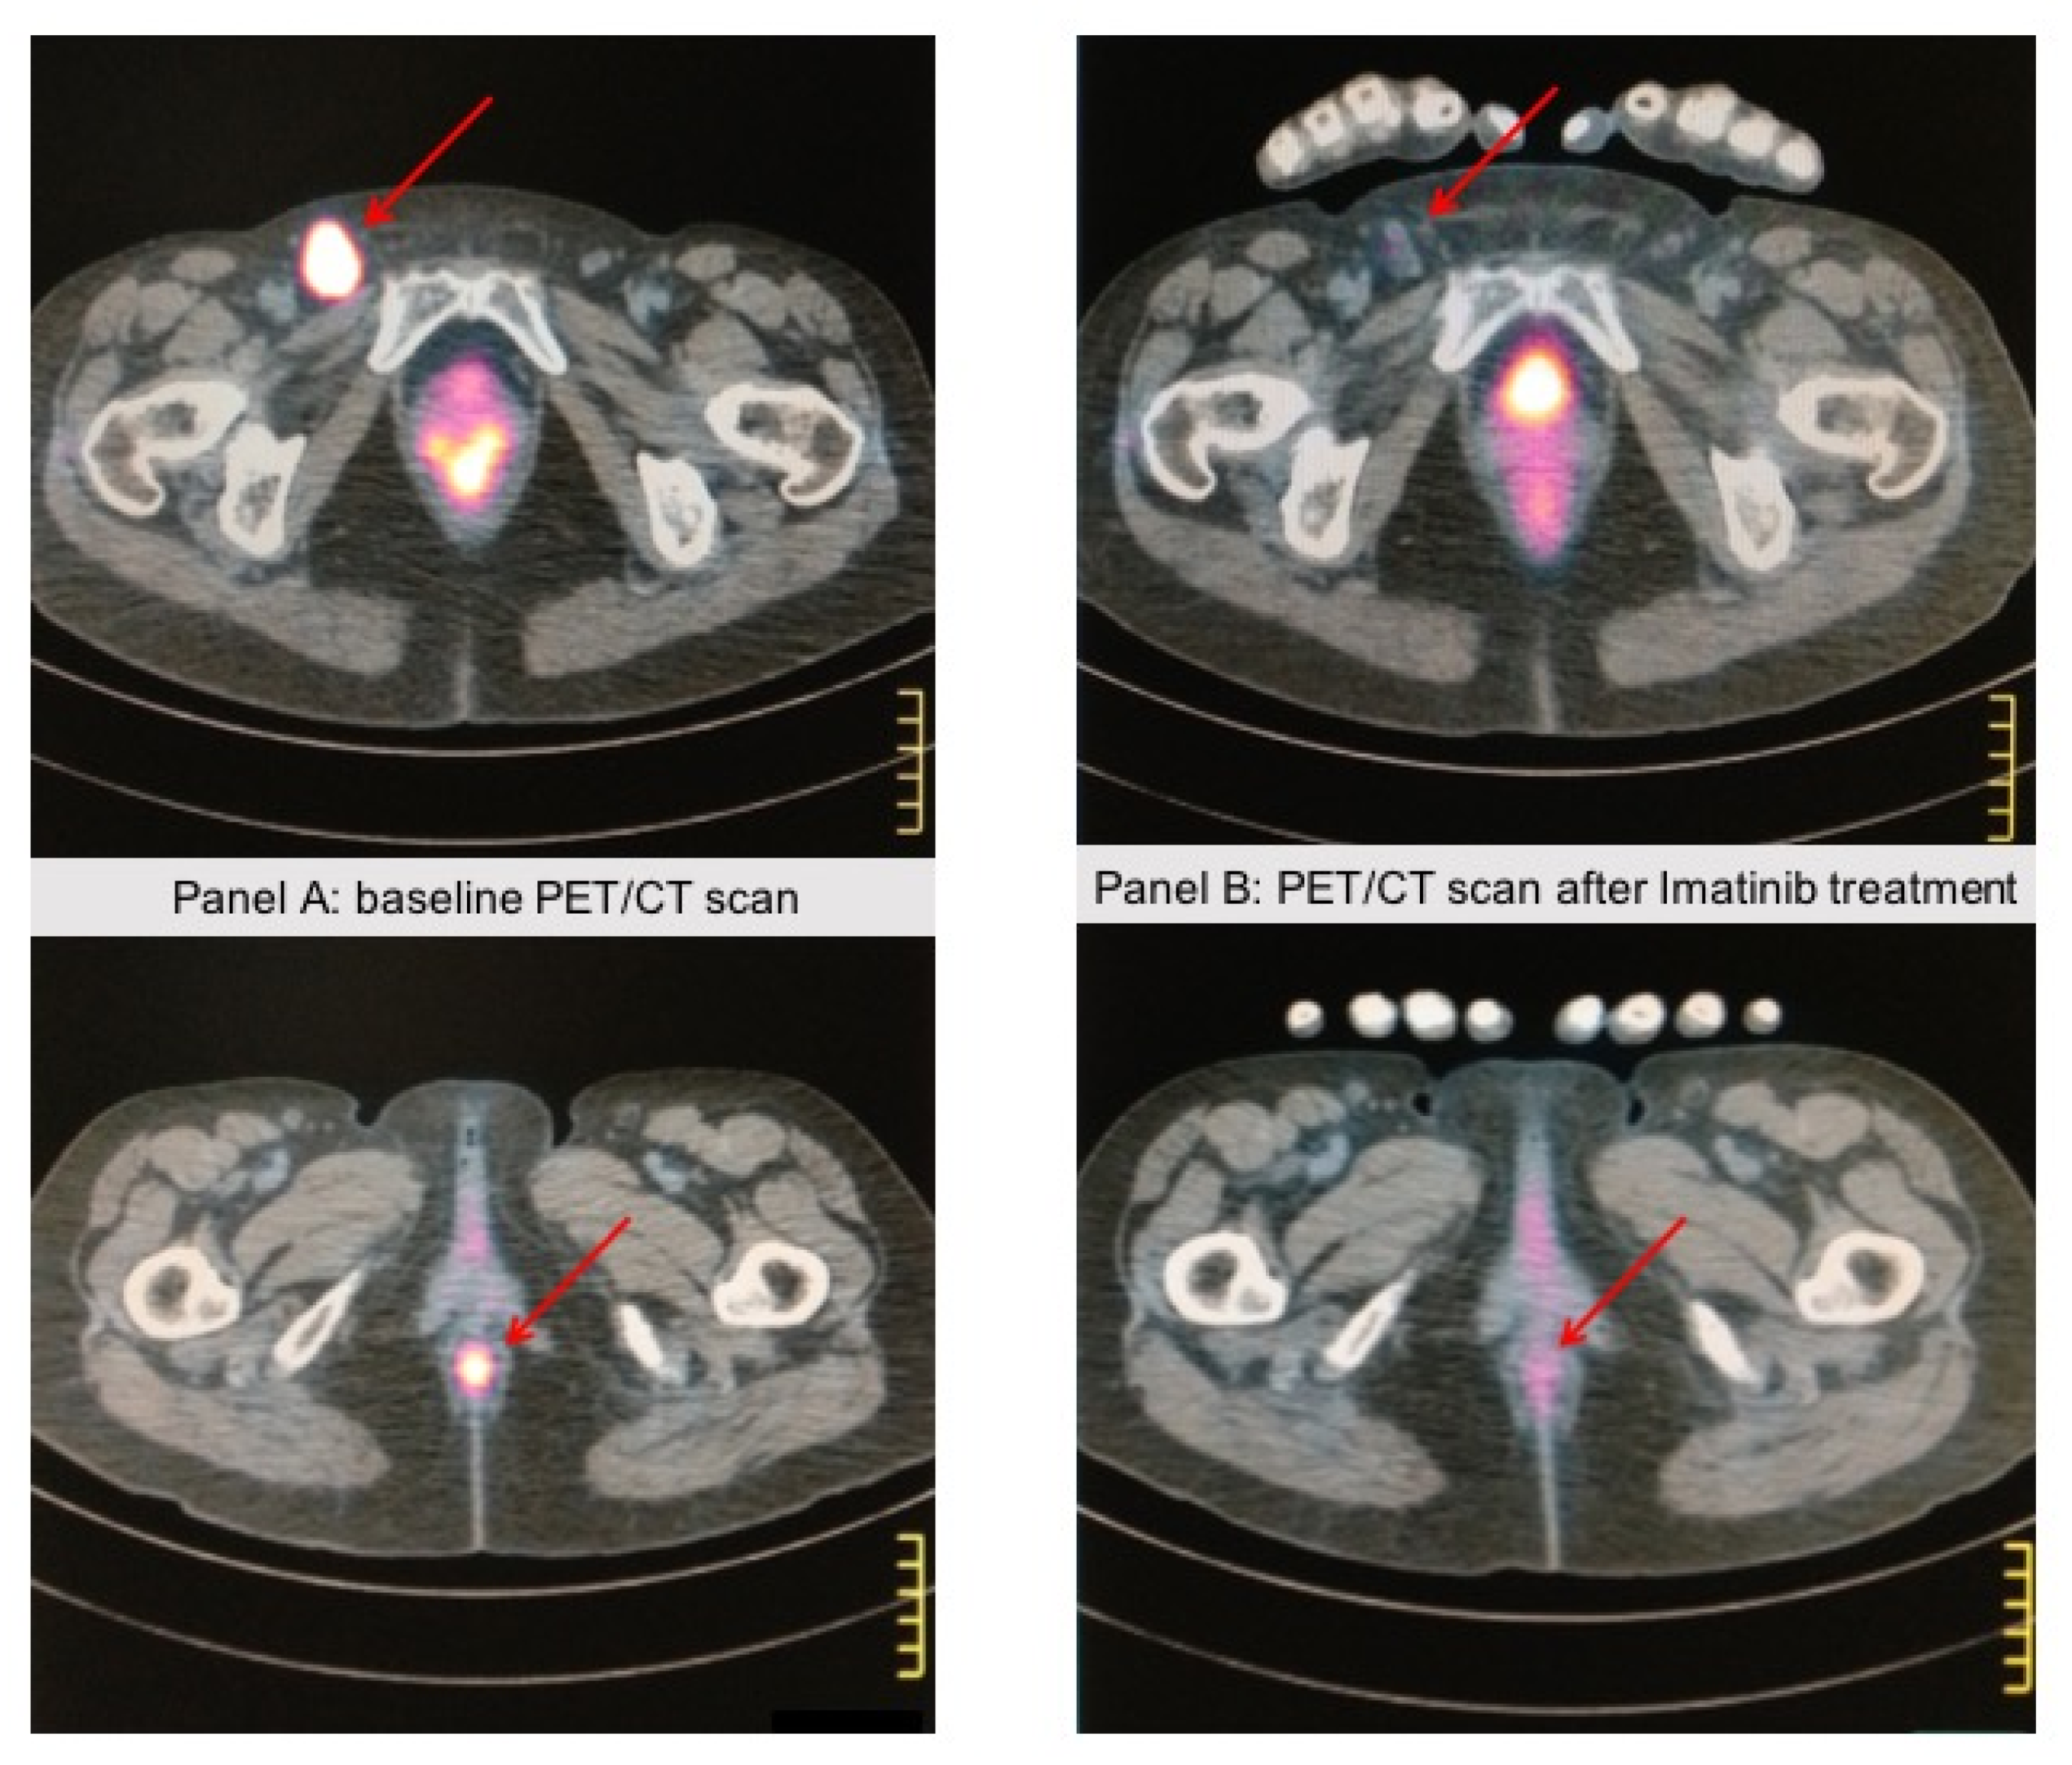

- Carvajal, R.D.; Antonescu, C.R.; Wolchok, J.D.; Chapman, P.B.; Roman, R.A.; Teitcher, J.; Panageas, K.S.; Busam, K.J.; Chmielowski, B.; Lutzky, J.; et al. KIT as a therapeutic target in metastatic melanoma. JAMA 2011, 305, 2327–2334. [Google Scholar] [CrossRef] [PubMed] [Green Version]

- Hodi, F.S.; Corless, C.L.; Giobbie-Hurder, A.; Fletcher, J.A.; Zhu, M.; Marino-Enriquez, A.; Friedlander, P.; Gonzalez, R.; Weber, J.S.; Gajewski, T.F.; et al. Imatinib for melanomas harboring mutationally activated or amplified KIT arising on mucosal, acral, and chronically sun-damaged skin. J. Clin. Oncol. 2013, 31, 3182–3190. [Google Scholar] [CrossRef] [Green Version]

- Steeb, T.; Wessely, A.; Petzold, A.; Kohl, C.; Erdmann, M.; Berking, C.; Heppt, M.V. c-Kit inhibitors for unresectable or metastatic mucosal, acral or chronically sun-damaged melanoma: A systematic review and one-arm meta-analysis. Eur. J. Cancer 2021, 157, 348–357. [Google Scholar] [CrossRef]

| KIT | Amplifications and missense mutations (Ex11 and Ex12-21) | 13% | similar rates in upper and lower body regions | Imatinib Dasatinib Nilotinib |